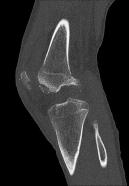

Question 3:

A 22-year-old soccer player sustains a twisting injury to his knee during a match. Radiographs reveal a small elliptical bone fragment adjacent to the lateral tibial plateau (Segond fracture). Based on this radiographic finding, which physical exam maneuver is most likely to be positive in this patient?

Correct Answer: Positive pivot shift test

Explanation:

A Segond fracture is an avulsion fracture of the anterolateral ligament (ALL) and lateral capsule from the lateral tibial plateau. It is highly pathognomonic (up to 75-100% predictive value) for an anterior cruciate ligament (ACL) tear. The pivot shift test is the most specific physical examination finding for assessing rotational laxity associated with an ACL-deficient knee.